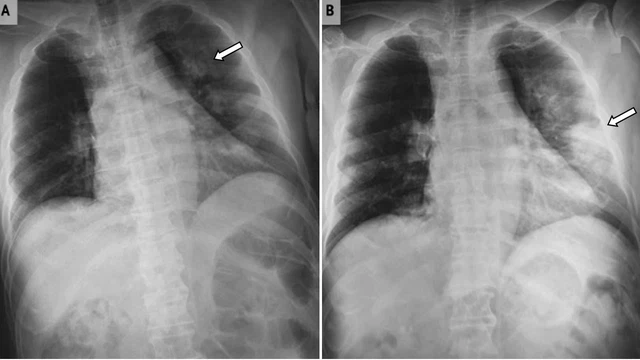

Trong y khoa, phổi trắng là hình ảnh mảng trắng bất thường trên X-quang hoặc CT scan, phản ánh những tổn thương đáng kể ở nhu mô phổi. Đây không phải bệnh lý riêng mà là dấu hiệu cảnh báo nhiều vấn đề hô hấp nguy hiểm như viêm phổi, lao hay ung thư phổi.